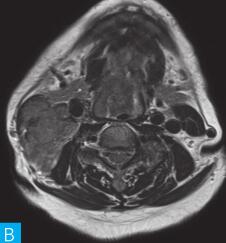

喉咽部MRI检查:病人采取仰卧位,横断位扫描为主,包括T1WI、T2WI及T2WI脂肪抑制序列,扫描范围自鼻咽部至喉咽以下,扫描层厚为3.5mm、层间隔0.35mm,矩阵512×512;辅以冠状位T2WI,矢状位T2WI序列及脂肪抑制序列,平扫后行横断位、冠状位及矢状位的增强扫描,造影剂量0.2ml/kg。见图1。

图1 咽喉部MRI:A.喉咽部MR横断面平扫T1WI;B.喉咽部MR横断面T2WI;C.喉咽部MR横断面T2压脂;D.喉咽部MR横断面增强T1WI;E.喉咽部MR冠状面T2WI;F.咽喉部MR冠状面增强T1WI